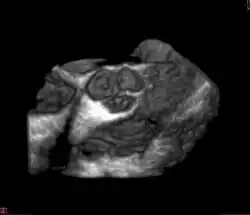

Die Aortenklappe (Valva aortae) ist eine der vier Herzklappen. Sie liegt in der Aortenöffnung (Ostium aortae), direkt am Ursprung der Aorta aus der linken Herzkammer und verhindert den Rückfluss des Blutes zu Beginn der Erschlaffungsphase (Diastole) des Herzens.

Die Aortenklappe besteht als Taschenklappe zumeist aus drei halbmondförmigen Taschen (Valvulae), die Bildungen der Intima (der innersten Schicht der Blutgefäße) sind:

Die Klappe liegt mit ihren Ausbuchtungen (Sinus) im Anfangsteil der aufsteigenden Aorta (Aorta ascendens). Auf Deutsch werden die Taschen entsprechend der Abgänge der beiden Herzkranzarterien aus den zugehörigen Sinus bezeichnet: rechtskoronare Tasche (am Abgang der rechten Herzkranzarterie), linkskoronare Tasche (am Abgang der linken Herzkranzarterie) und akoronare Tasche (Sinus ohne abgehende Herzkranzarterie). Die Aortenklappe bildet sich beim Menschen gemeinsam mit der Pulmonalklappe in der 5. bis 7. Woche der Embryonalentwicklung. Manchmal besteht die Aortenklappe nur aus zwei Taschenklappen.